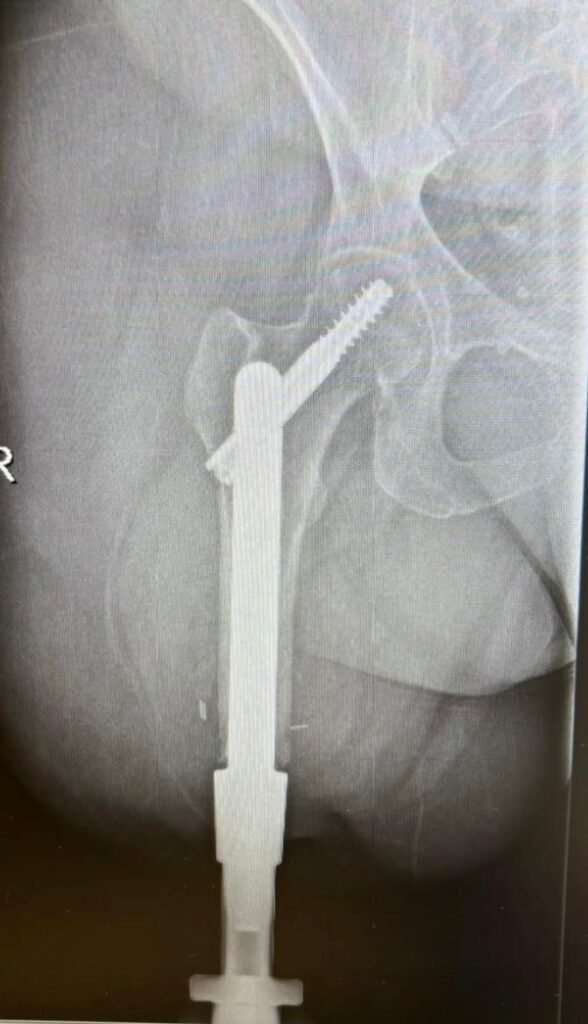

Este nuevo sistema permite la fijación del implante, elaborado de una aleación de titanio, directamente al hueso. De esta forma, la unión de la prótesis osteointegrada es mucho más estable y permite un rango de movimiento completo de la articulación.

Para la intervención se realiza el diseño de un implante personalizado, creado a medida para la paciente en base a sus características físicas. La cirugía se completa con un programa de rehabilitación, que tiene como objetivo conseguir la adaptación a la prótesis externa para adaptarse a caminar con este implante.

El sistema utilizado es una de las últimas versiones de prótesis de osteointegración que hay en el mercado. Fue diseñada en Países Bajos y ya se han realizado más de 500 implantaciones en todo el mundo.